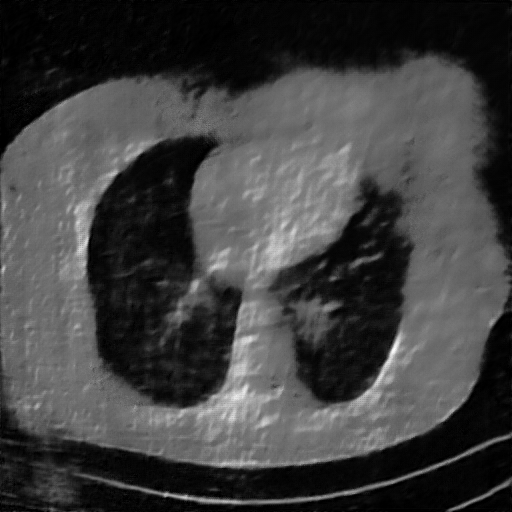

Fig. 4 presents the reconstruction results and residual images obtained by different methods for limited-angle reconstruction. As can be seen, the learning-based methods outperform the direct method and TV model, which exhibit serious artifacts in the missing angle region. Although the denoiser introduced by the FBP-Unet can somehow deal with the noises, the result still presents obvious artifacts. Compared to the SIPID, PD-net and FSR-nets, our LRIP-net1/2 can better preserve the image details and edges with less information left in the residual images. Thus, both the quantitative and qualitative results confirm that the low-to-high double-resolution strategy can improve the reconstruction accuracy for the limited-angle reconstruction problem.

We observe that the low-resolution image prior plays an important role in our method. More specifically, we compare the results of our LRIP-net with respect to different low-resolution priors, which are obtained by down-sampling rate of 1/2, 1/4, and 1/8, respectively. As can be seen in Table III, the best reconstruction results are obtained with the image prior reconstructed by the down-sampling rate of for 150∘, 120∘ and 90∘ limited-angle reconstruction. The visual comparison based on different image priors are also provided in Fig. 5, where obviously less artifacts are left in the reconstruction image by LRIP-net1/8. By comparing the running time, it is easy to see that the smaller the low-resolution image prior, the faster the LRIP-net works.